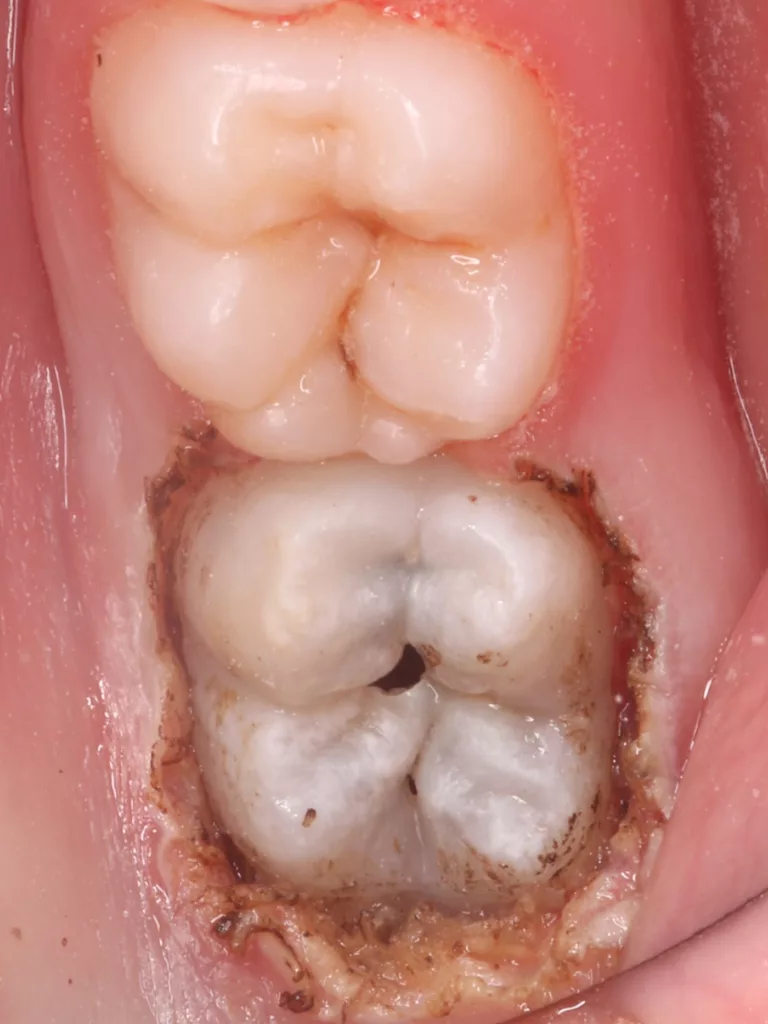

Bei routinemäßigen Röntgenkontrollen ergeben sich manchmal Zufallsbefunde unklarer Genese. So stellt sich beispielsweise bei der Betrachtung der Abbildung 1 die Frage, wie sich ein Zahnhartsubstanzdefekt so schnell entwickeln konnte. Ein weiteres Röntgenbild (Abb. 2), das vor dem Zahndurchbruch aufgenommen wurde, zeigt jedoch, dass es sich in diesem Fall nicht um Karies, sondern um die sogenannte präeruptive intrakoronale Resorption (PEIR) handelt. Für diesen Befund finden sich in der Fachliteratur auch noch andere Bezeichnungen wie „idiopathic external resorption of unerupted permanent teeth“ [1], „intra-follicular caries“ [2], „radiolucent lesions resembling caries“ [3], „occult caries“ [ 4] oder „pre-eruptive caries“ [5].

V. Slabkovskyi, O. LiutikovJahr vor dem Durchbruch des Zahnes 36.

Das fünfjährige Mädchen stellte sich 2017 zur jährlichen Routinekontrolle vor. Im Rahmen der Untersuchung wurden Röntgenaufnahmen der Milchmolaren gemacht (Abb. 2). Der klinische und radiologische Befund der vor uns früher gelegten Kompositfüllungen war gut, es wurde allerdings eine PEIR an den noch nicht durchgebrochenen ersten bleibenden Molaren festgestellt (Abb. 2). Den Eltern wurde empfohlen, sich unverzüglich bei Beginn des Durchbruchs der ersten Molaren erneut zur Behandlung vorzustellen. Ein Jahr später erschien die junge Patientin schmerzfrei zur Kontrolle. Der Zahn 36 war noch teilweise mit Gingiva bedeckt. Auf einer neuen Röntgenaufnahme (Abb. 1) wurde die PEIR-Läsion mit unveränderter Größe in pulpanahen Bereichen bestätigt (Grad 3 der Läsion nach Seow). Der Zahnschmelz sah intakt aus, es konnte kein pathologischer periapikaler Befund bei den noch nicht ausgewachsenen Zahnwurzeln festgestellt werden. Daraufhin wurden die verschiedenen Behandlungsmöglichkeiten von Fissurenversiegelung bis Vitalerhaltung der Zahnpulpa mit den Eltern des Kindes besprochen.